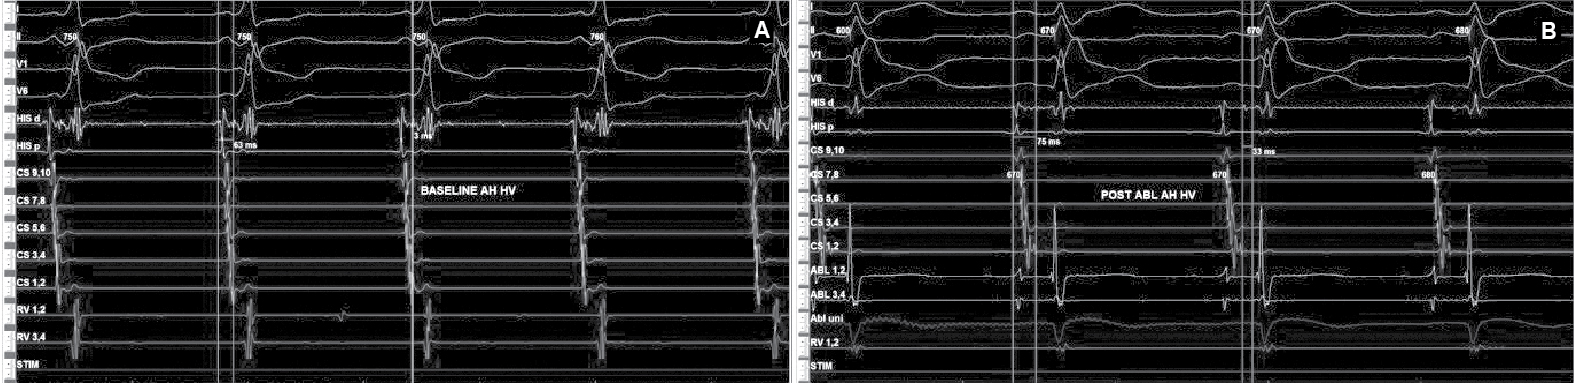

After written informed consent, patient was taken for electrophysiological study. Two quadripolar diagnostic catheters were advanced under fluoroscopy to His bundle region and right ventricular apex. One decapolar catheter was advanced into the coronary sinus. During the electrophysiological study at baseline, atrial-His bundle (AH) and His-ventricular (HV) intervals were 85 ms and 3 ms in sinus rhythm, respectively. There were no atrioventricular (AV) conduction abnormalities. A narrow complex tachycardia (tachycardia cycle length [TCL] = 400 ms) was easily induced during catheter placement with following features: initiation of the tachycardia with a critical AH interval, fixed 1:1 ventriculoatrial (VA) conduction, concentric retrograde activation with VA interval of 37 ms, a post-pacing interval (PPI, 576 ms)–TCL (406 ms) >115 (170 ms) and ventricular overdrive pacing resulted in a VAHV response. His synchronized and early premature ventricular contraction (PVC) did not reset the tachycardia. His synchronized premature atrial contraction (PAC) also failed to reset the tachycardia. The tachycardia was reproducible and consistent (Fig. 2). After confirming the diagnosis of typical AV nodal re-entrant tachycardia (AVNRT) a decision was taken for slow pathway ablation. Using a steerable ablation catheter, with the help of intracardiac electrograms (EGMs) and using fluoroscopy, the region of the slow pathway was identified. Radiofrequency applications were made in the region of the slow pathway while constantly monitoring temperature, impedance, ECG and intracardiac EGMs, monitoring for fast junctional conduction and radiofrequency energy was halted if there was evidence of VA block. Radiofrequency ablation resulted in a junctional rhythm with intact AV conduction, which is a typical response. The AV nodal slow pathway was successfully modified (Fig. 3).

Figure 6. Intracardiac intervals baseline (A) showed HV interval of 3 ms that was normalized (B) after successful accessory pathway ablation.